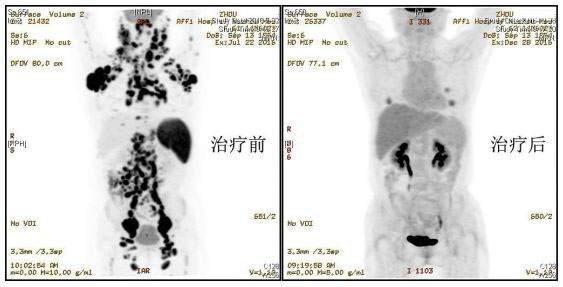

患者周华(化名),女,62岁,2016年4月因“全身多发肿块”经病理检查等确诊为弥漫大B细胞淋巴瘤(生发中心起源,Ⅳ期),染色体示复杂核型。先后予多次化疗,病情控制不理想,PET-CT显示双侧腮腺区、鼻咽部、口咽部、双侧颌下、颏下、胸锁乳突肌内缘、双侧颈后三角、锁骨上区、右侧肩胛部皮下、双侧腋窝、纵隔、两侧肺门、右侧心膈角、双侧膈角后、肝胃间、胰腺周围、肠系膜根部、腹主动脉周围、右侧结肠系膜区、双侧髂血管周围、双侧腹股沟区、直肠周围系膜区多发淋巴结肿大,葡萄糖代谢明显增高,提示肿瘤全身广泛侵犯,预后极差。

该患者常规治疗已无明显疗效,即使行挽救性自体造血干细胞移植预后也极差。患者家属把最后一线希望寄予了CAR-T细胞治疗。2016年8月患者输注了IL-7+IL-15联合培养的CD19 CAR-T细胞,肿块仅短暂缩小后又再次肿大。2016年9月改用IL-2培养的CD19 CAR-T细胞输注治疗,患者肿块依然无明显变化,此时患者及家属已陷入了绝望,准备放弃治疗。医疗组经过反复讨论,结合国际前沿理论决定尝试CD20 CAR-T治疗。2016年11月输注CAR-T细胞后半月,患者全身肿大淋巴结已完全消退,并且治疗过程副作用轻微。目前已回输细胞一个月,复查PET-CT显示多处肿块已消失,患者达到了完全缓解。曹江博士认为该例患者的治疗经验提示序贯或联合多靶点CAR-T细胞治疗将有望给更多的晚期淋巴瘤患者带来福音。